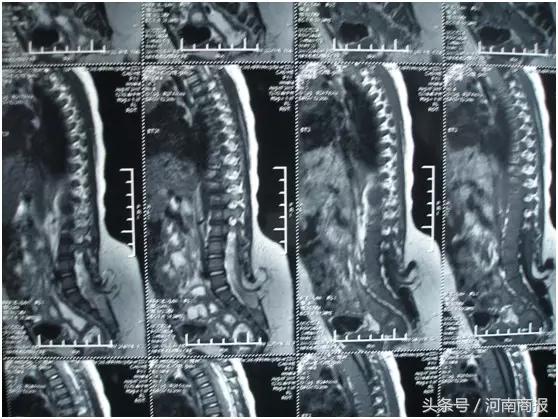

入院后不久,马云富就为涛涛进行了脂肪瘤切除,以及脊髓粘连松解、脊髓拴系松解手术。手术2个月后,涛涛大小便功能出现不同程度的恢复,肢体活动也比以前有了好转。

“患儿得的是脊柱裂,是神经管畸形的一种。”据马云富介绍,脊柱裂属于先天性疾病,其发病率非常高,目前已跃居新生儿缺陷的首位,“这个病以前也有,只不过随着磁共振在临床的普遍应用,它的发现率现在是越来越高了。”